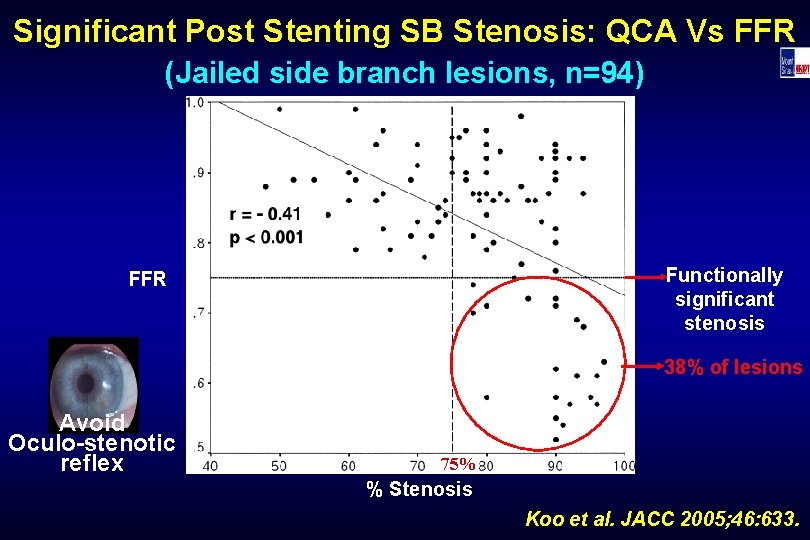

Significant Post Stenting SB Stenosis: QCA Vs FFR (Jailed side branch lesions, n=94) Functionally significant stenosis FFR 38% of lesions Avoid Oculo-stenotic reflex 75% % Stenosis Koo et al. JACC 2005; 46: 633.